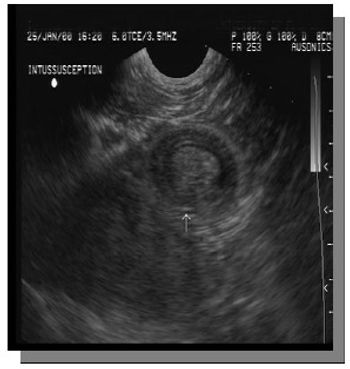

Abdominal pain in the foal can be a frustrating diagnostic challenge as the differential diagnosis are extensive. Abdominal pain can progress rapidly leading to septicemia or even death.

Abdominal pain in the foal can be a frustrating diagnostic challenge as the differential diagnosis are extensive.